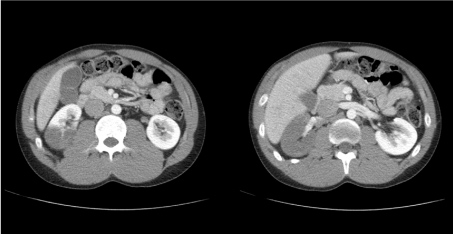

A 22-year-old African American male college student presented with acute abdominal pain radiating to the right flank with associated fever, dark urine, and non bilious non bloody vomiting. There was no dysuria or change in bowel habits. Medical history was notable for nephrotic syndrome due to biopsy-proven minimal change disease diagnosed at age 17, which was in remission with the use of tacrolimus and prednisone. He had ingested synthetic cannabinoids the night before, and experienced a brief episode of diaphoresis, palpitations, and anxiety. Exam was notable for right CVA tenderness. Labs were remarkable for leukocytosis of 17,400/microliter and microscopic hematuria. Urine protein to creatinine ratio suggested proteinuria of 1.2 g/day. Cardiolipin antibodies and homocysteine levels were not elevated. Factor V Leiden and prothrombin gene G20210A mutation was negative. Abdominal CT with contrast showed an acute right kidney infarction, and the patient was placed on heparin gtt (Figure 1). Angiography showed an 18 mm thrombus in the distal aspect of the right main renal artery, with impaired perfusion to the superior two-thirds of the kidney but sparing of the inferior pole due to an accessory renal artery (Figure 2) [1-6].

Figure 1: Contrast CT of abdomen and pelvis. Axial view demonstrating showing acute right kidney infarction, with sparing of the inferior pole.